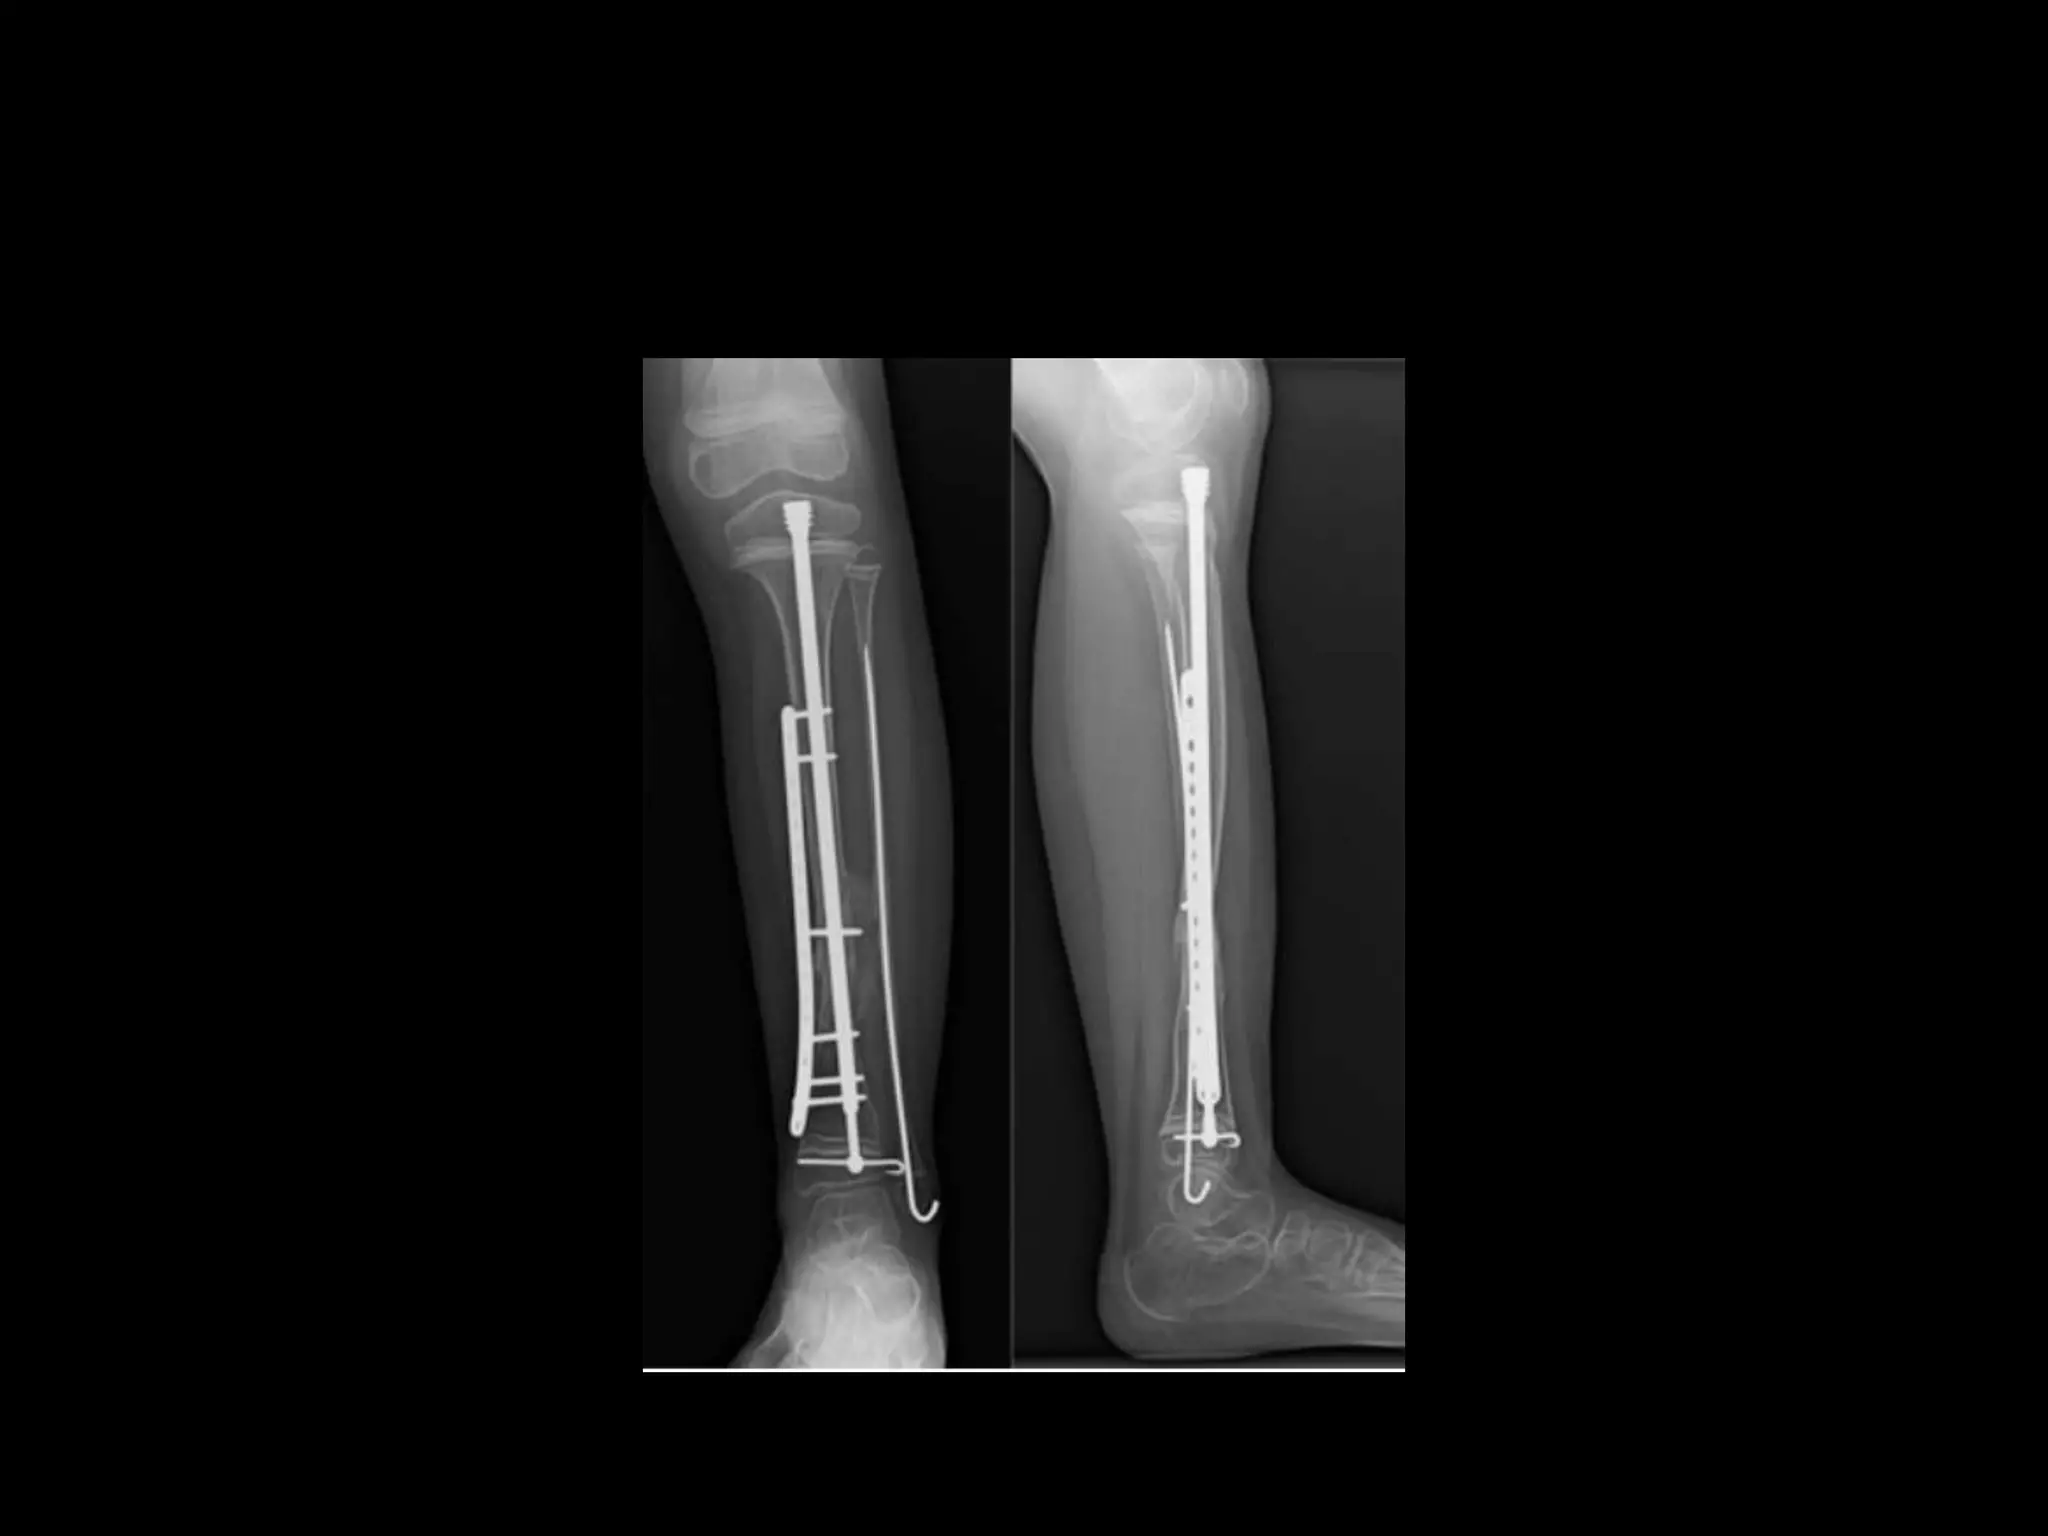

Intra medullary fixation

• The procedure of choice for the first attempt

to gain union entails resection of

pseudoarthrosis,shortening and fixation with

an intramedullary rod and autogenous bone

grafting.

Williams technique

• Williams conceived the novel technique of

threaded male and female components of the

rod that when joined,can be placed antegrade

through the pseudoarthrosis site and out the

bottom of the foot.

• After retrograde insertion back in to the proximal

intra medullary of the tibia the male end is

unscrewed and removed from thebottom of the

foot with the female threaded rod left

intraosseously in the tibia or across the ankle in

talus/calcaneus.

• The undesirable effect of ankle immobilisation

by IM fixation is thought ot be necessary evil

to adequately immobilise the small distal

fragment.

• As the tibia grows the foot and ankle may

eventually grow off the distal end of the IM

rod and thus allow ankle to regain motion